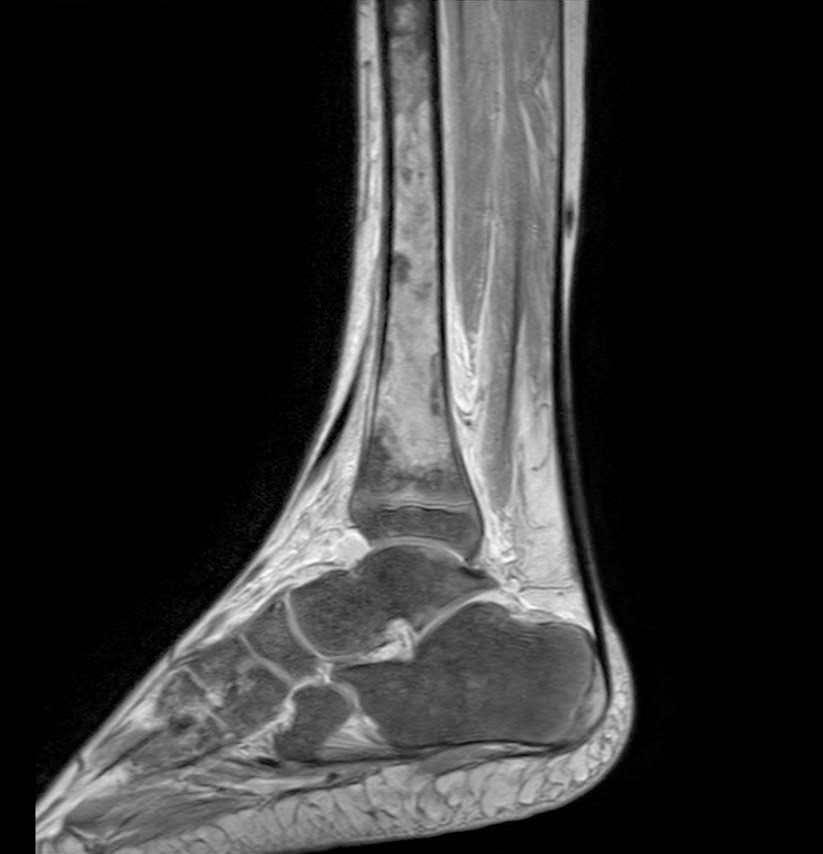

Caso interesante #3

Paciente 1 (Caso de referencia)

Masculino 17 años

Caso interesante # 3